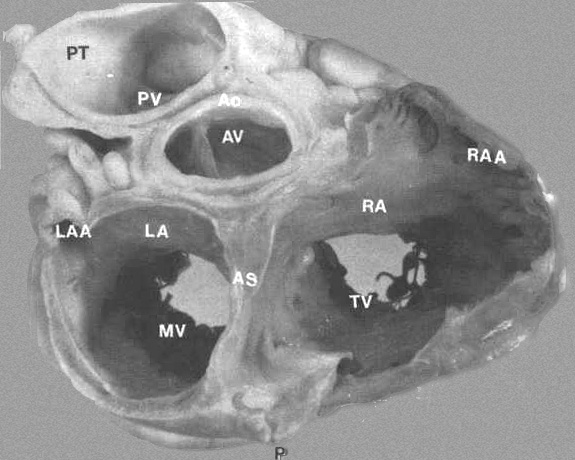

FIGURE 3:

Transverse section through base of heart showing relationship

of various chambers and great vessels. A = anterior; AO = aorta;

AS = atrial septum; AV = aorta; LA = left atrium; LAA = left

atrial appendage; MV = mitral valve; RA = right atrium; RAA

= right atrial appendage; P = posterior; PT = pulmonary trunk;

PV = pulmonary trunk; PV = pulmonic valve; TV = tricuspid valve.

From Hurst’s THE Heart, Eighth edition, page 61.)